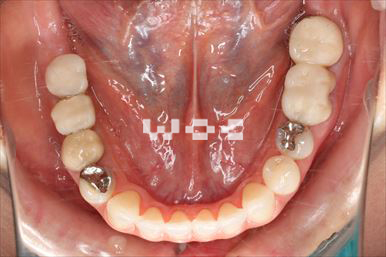

開咬開咬

上下舌側矯正を希望。上顎両側第一小臼歯の抜歯としたが上顎右側第二小臼歯は治療した歯であったため、抜歯部位を変更。治療の難度が上がったため治療期間が少し延長しました。

- 年齢:33歳女性

- 主訴:出っ歯、前歯で噛めない

- 基本矯正料金:1,295,000円

- 治療期間:2年8ヶ月

- 抜歯部位:上顎右側第二小臼歯、左側第一小臼歯